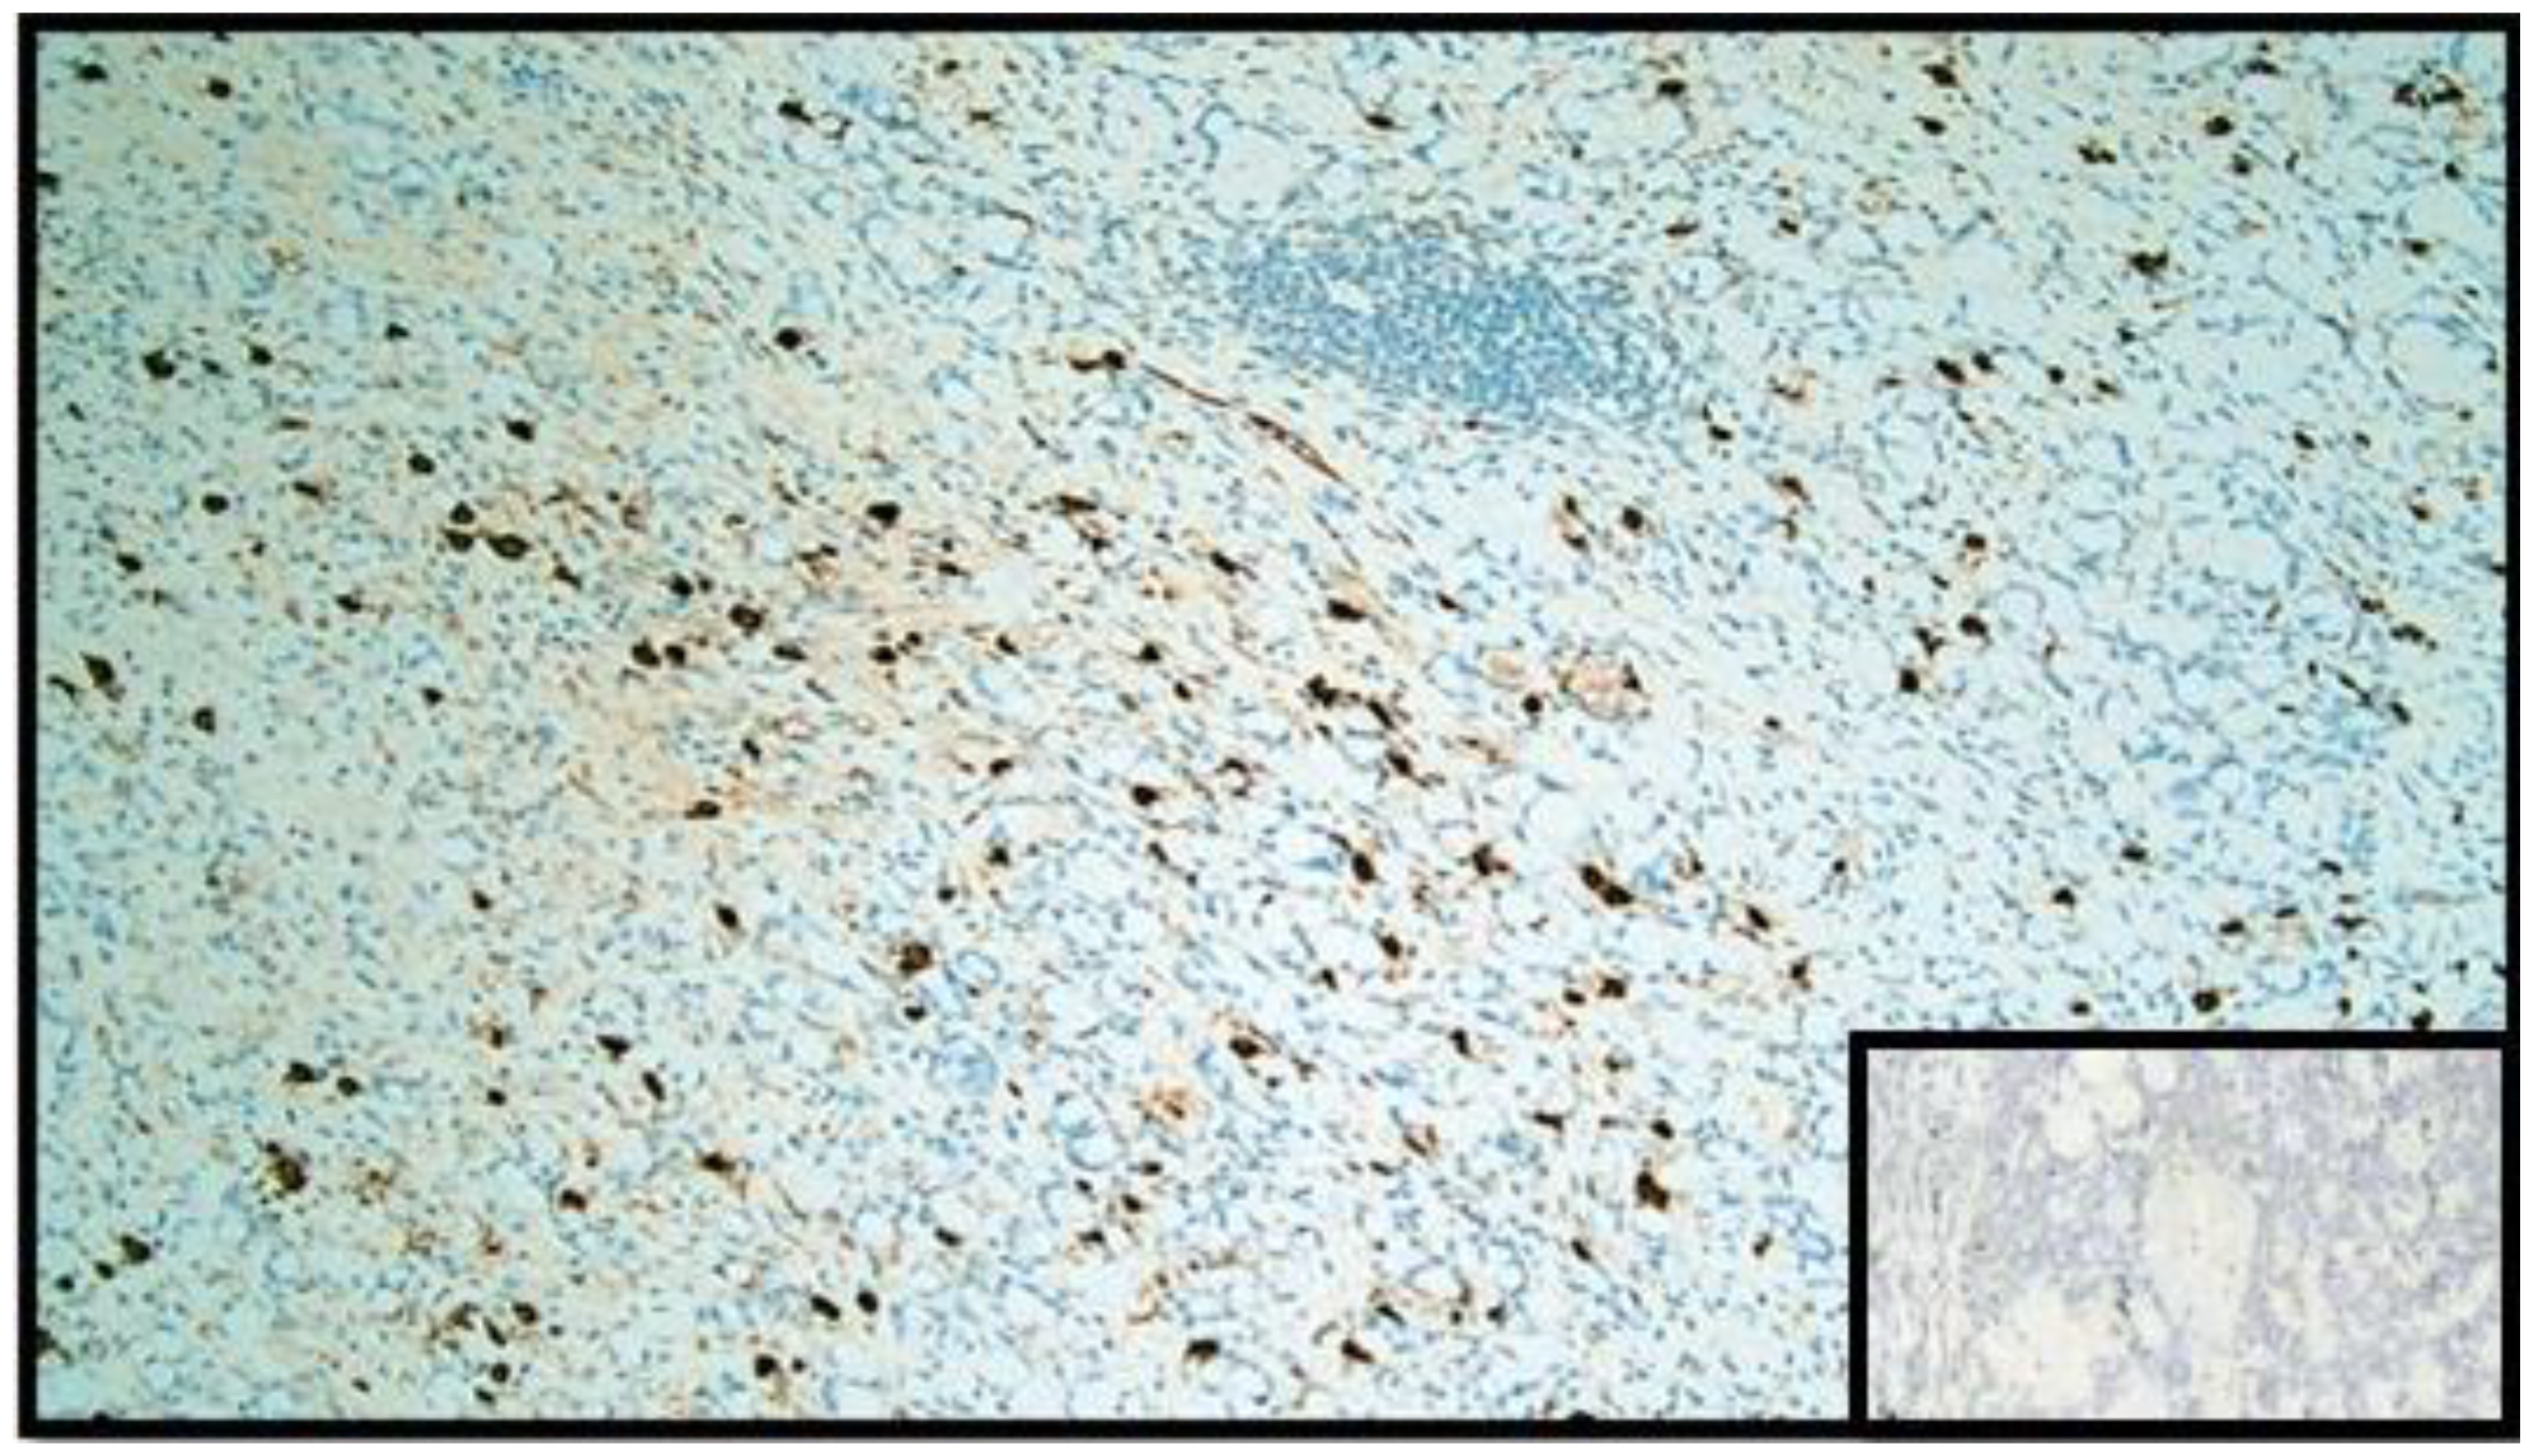

Figure 5.

Immunohistochemical reaction with anti-chromogranin A antibody. Note the widespread positivity in the GCC component (IHC, original magnification: 20×). Box: negative control.